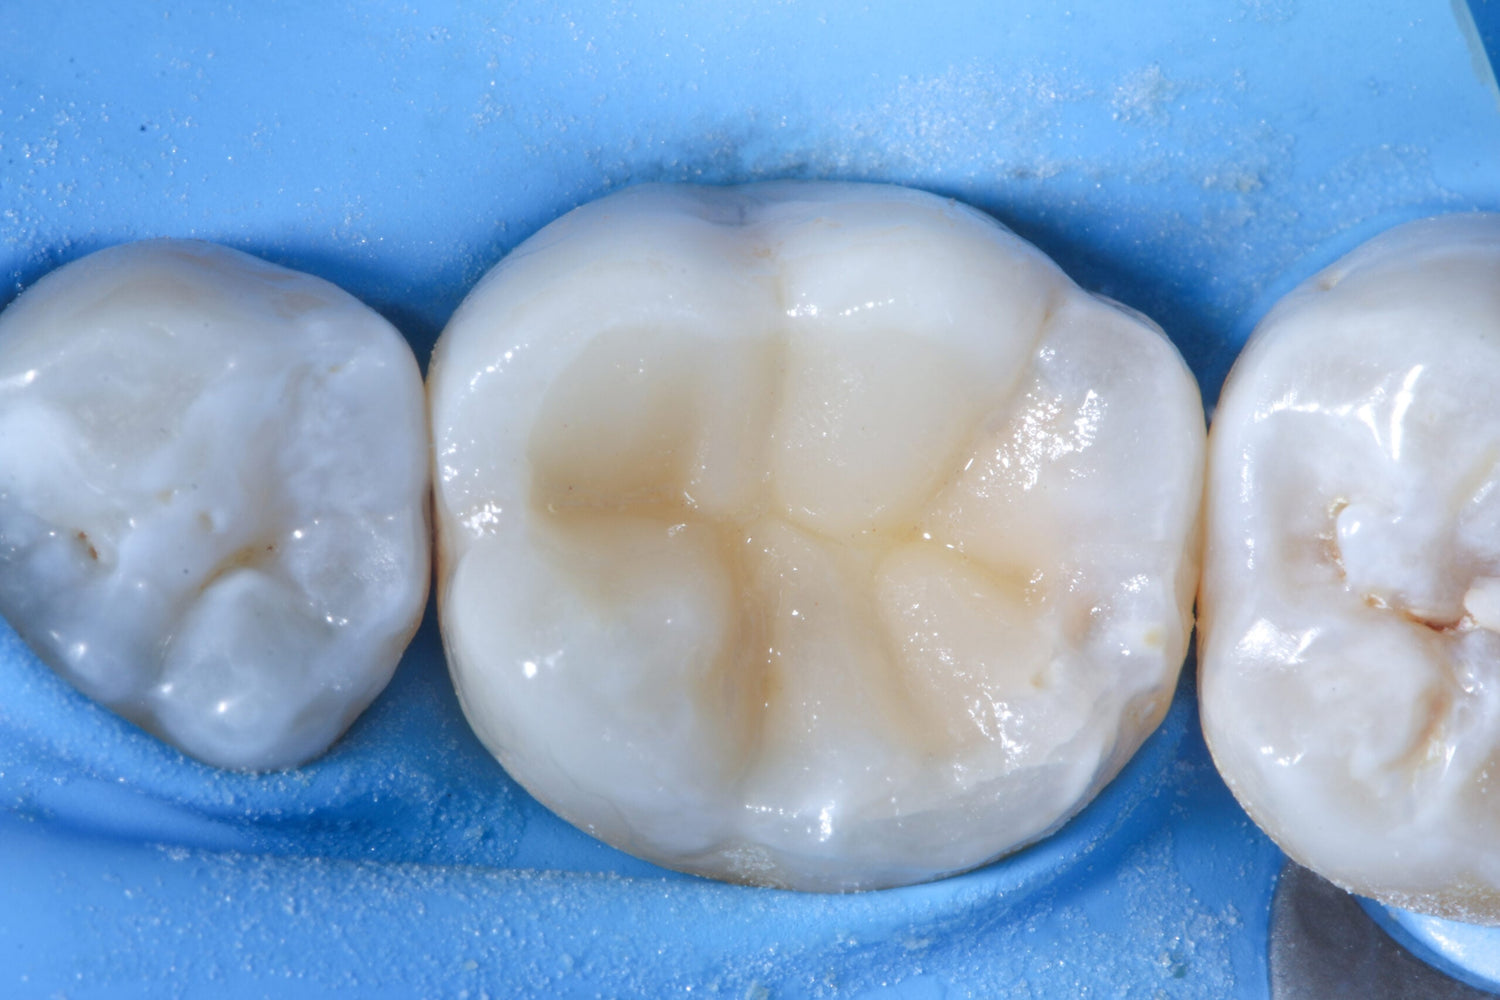

The procedure began with local anaesthesia of the treatment site. A strong advocate of rubber dam use, Benjamin then applied a rubber dam to ensure complete isolation and prevent moisture contamination.

As the affected molar already had a filling, the existing restorative material was removed with a diamond bur. He then eliminated the secondary caries using an EndoTracer, switching to a hand instrument for precise finishing of the remaining tooth structure.

The stages of a partial pulpotomy in pictures